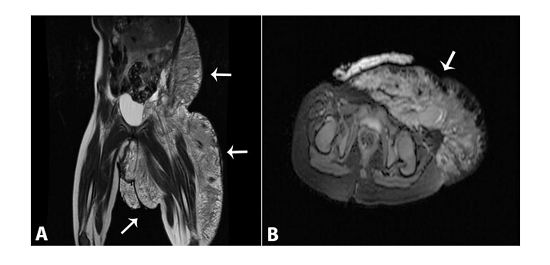

Cytogenetic analysis revealed normal karyotype by genetic amniocentesis. Detailed information was given to the parents about the possible postnatal prognosis. They decided to continue with the pregnancy. Follow-up was uneventful until the 36th week of gestation. The dimensions of the cystic mass remained the same. At 36 weeks gestation, oligohydramnios was diagnosed, and the fetus was small for that gestational age. A 2600 g infant was delivered at 38 weeks’ gestation by cesarean section because of the mother’s previous history of cesarean delivery. In the postnatal examination, a multicystic and translucent mass was seen which had 5 cm maximum diameter without any skin lesion. The mass extended from the left inguinal region to the left thigh, and a hemangioma was detected on the left inguinal region of 25 mm width. No cyst damage occurred during the delivery. The Apgar scores were 7 and 9 after 1 and 5 min, respectively. MRI reported an inguinal lymphatic malformation, and an ultrasound revealed there was no fetal anomaly and no apparent invasion of the mass into the abdominal cavity and the intra-abdominal organs. The MRI detected lymphatic-venous vascular malformation, which was associated with the femoral vein (Figure 3). It was not necessary to schedule any pediatric surgical intervention.

To the best of our knowledge, there are four published case reports similar to ours involving a fetal abdominal lymphatic malformation extending to an extremity having been diagnosed by prenatal sonography. In three cases, pregnancy was terminated, and in one case, postnatal surgical resection or sclerotherapy was successfully performed.14,15 Differently from these previous reports, in our case, an isolated inguinal lymphatic malformation was observed without an intra-abdominal component, and was associated by an abnormal femoral vein.